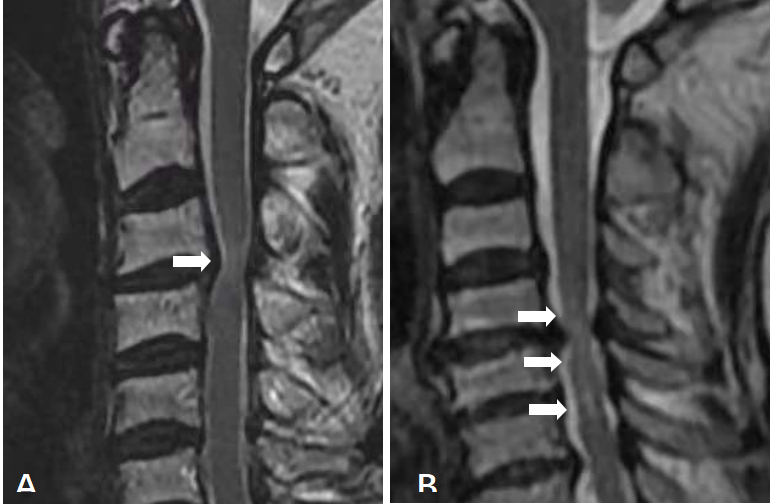

3.5 髓内高信号(increased signal intensity,ISI)

依据Yukawa等提出的评估方法,进行适当修改后,将受压迫节段髓内ISI被评为三度:度,无高信号;1度,轻度且单节段高信号;2度,重度或多节段高信号(图4A、4B)。

图4.髓内高信号分级(ISI)。A:1度ISI,轻度且单节段高信号;B:2度ISI,重度或多节段高信号